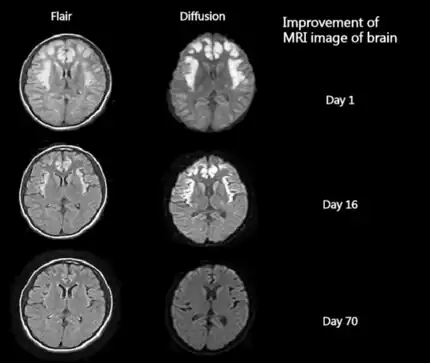

![]() | |

| The urea cycle. The enzyme OTC, labeled prominently in the center of the mitochondria, is deficient in patients with this disorder. | |